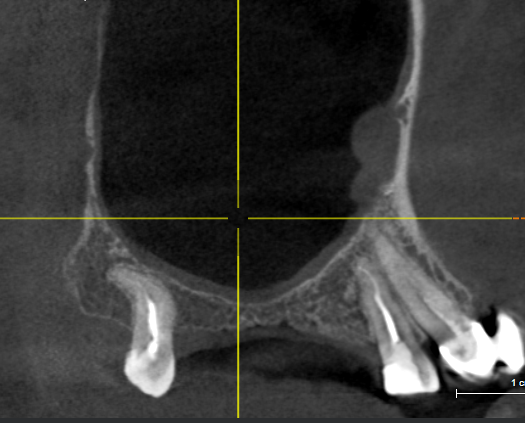

На верхней челюсти у пациента отсутствовали зубы 1.4,1.5 и 1.6. В области зубов 1.7 и 1.8 обширная радикулярная киста, оттесняющая гайморову пазуху. Выполнена цистэктомия с удалением несостоятельных зубов 1.7 и 1.8, заполнение полости кисты остеокондуктивным костным материалом, имплантация в позиции 1.4 и 1.5. Имплантация в области 1.6 и 1.7 будет выполнена после интеграции костного материала